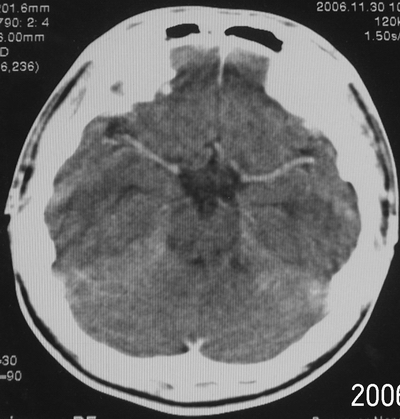

增强后

患者、男、18y,头痛5天入院。

左小脑、右丘脑区低密度影,无明显强化及占位表现,男18y,先考虑脑部炎性病变,如脑炎、血行播散性感染等,建议结合临床如脑脊液检验。

单独看左侧小脑半球的不规则形囊性低密度灶,从发病部位、年龄以及无强化、无占位效应的特点可以考虑毛细胞瘤型星形细胞瘤。同样,如果单独看右侧丘脑的近圆形低密度,也可以考虑囊变形星形细胞瘤。只是胶质细胞瘤一般为单发直接浸润、蔓延生长,而不是在脑内同时出现多个病灶,且瘤周没有一点儿水肿,暂时不予以考虑。

脑炎倒是首先可以考虑,只是临床症状、病史不很符合,建议狼兄仔细了解病史以及其他临床资料。

同时,现在已经进入冬天,一氧化碳中毒也需要考虑进去。不知道增强是什么时间做的,与平扫间隔几天?如果中间时间比较久而且进行吸氧等治疗,则平扫所示右侧颞叶密度比较低、右侧小脑半球以及脑桥也似有片囊状低密度,但在增强却没有发现就可以比较合理的解释了。